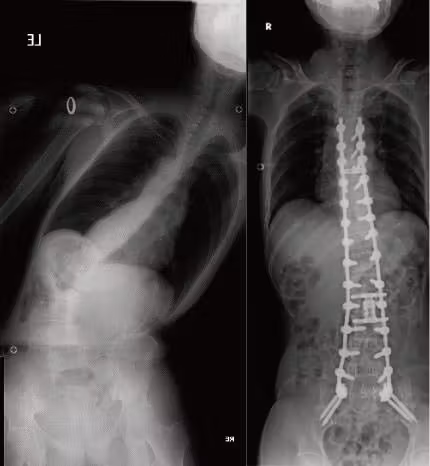

成人脊柱変形に対する矯正固定術

小児期側弯症の遺残、加齢に伴う椎間板変性による変性側弯症、椎体骨折後の変形などに対して、保存療法から手術療法まで対応しています。高齢患者さんには、二段階手術や身体への負担が少ない低侵襲固定手術、骨粗鬆症治療を組み合わせることで、合併症低減と効果的な矯正の両立を目指しています。